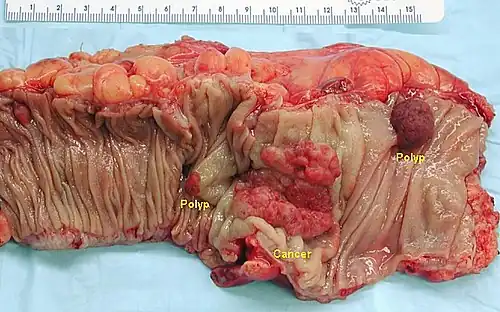

Der Dickdarm ist mit über 60000 jährlichen Neuerkrankungen in Deutschland nach der Prostata und der Brustdrüse der dritthäufigste Entstehungsort von Krebs, dem kolorektalen Karzinom.[50] Die Ursachen sind nicht genau bekannt, als Risikofaktoren gelten Rauchen, Bewegungsmangel, Übergewicht, Alkohol und rotes Fleisch.[50] Darüber hinaus gibt es seltene erbliche Formen wie die familiäre adenomatöse Polyposis oder das hereditäre nicht-polypöse kolorektale Krebssyndrom. Das gängige Modell der Entstehung von Dickdarmkrebs geht von einer Adenom-Karzinom-Sequenz aus. Das bedeutet, dass in einem mehrstufigen Prozess durch genetische Veränderungen das Drüsenepithel des Dickdarms entartet: Dafür reicht eine Zelle, die sich wegen dieser genetischen Veränderungen unkontrolliert teilt. Zunächst entsteht so ein gutartiger Tumor, ein Adenom, der bei der Koloskopie als Dickdarmpolyp auffällt. Die Zellen des Adenoms sind aber anfällig für weitere Genmutationen, sodass irgendwann Krebszellen entstehen, die bösartig in das umliegende Gewebe einwachsen und sich schnell teilen. Über 90 % der kolorektalen Karzinome gehen aus Adenomen hervor, weswegen die Entfernung eines Adenoms immer angezeigt ist.[51]